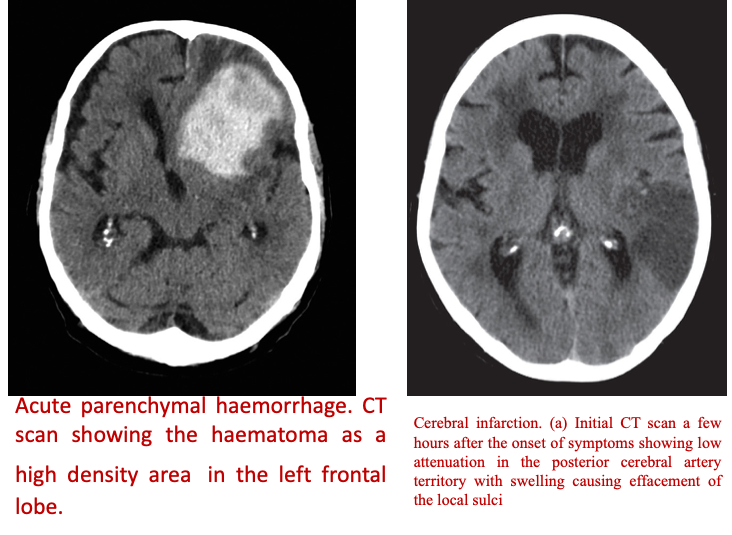

Irregular hypotenuse Acute positive mass effect infarction vs concave

MMA vessel left /-/ contralateral shift - hypodense acute infacrtion